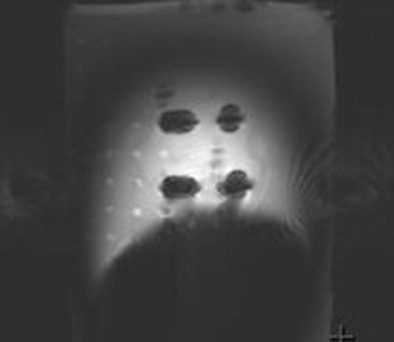

![]() |

| Deflection angle test performed on the armor-piercing bullet (No. 32) containing a steel core. The deflection angle is 90°, indicating the presence of substantial translational attraction. All images courtesy of Dr. Russell Dedini. |